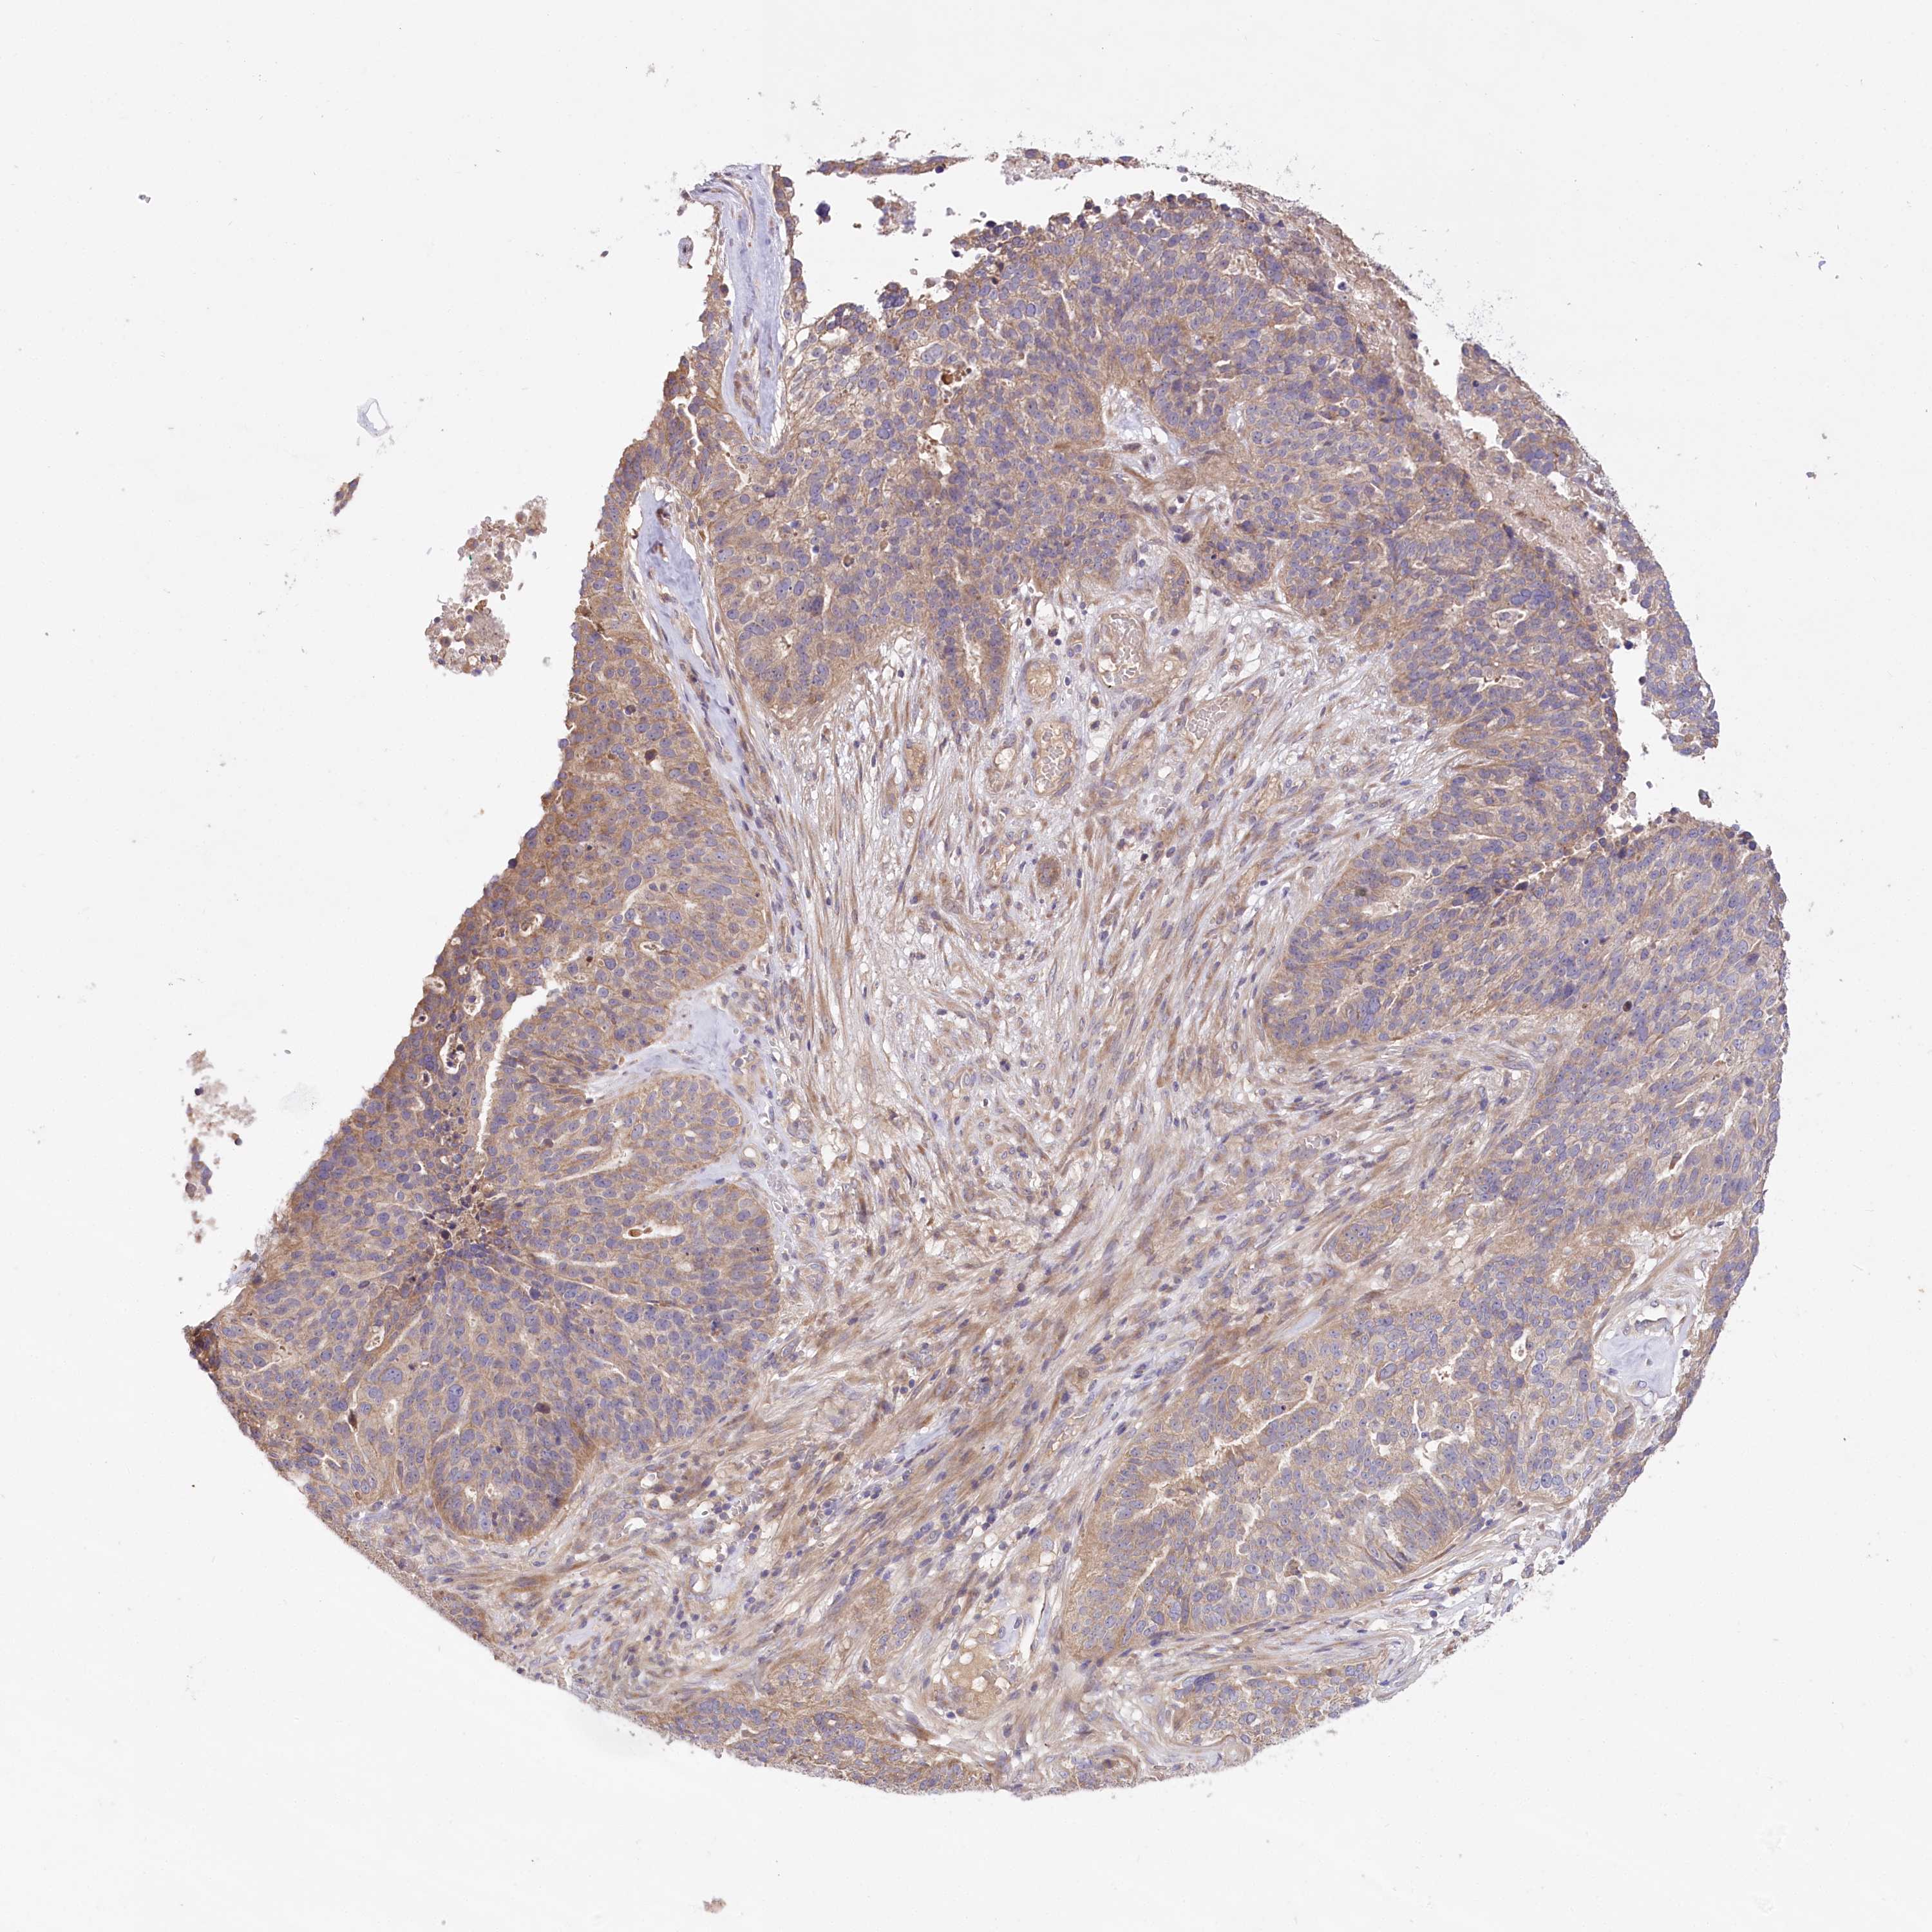

OVARIAN CANCER - Protein expressioni

A mouse-over function shows sample information and annotation data. Click on an image to view it in a full screen mode. Samples can be filtered based on level of antibody staining by selecting one or several of the following categories: high, medium, low and not detected. The assay and annotation is described here.

Note that samples used for immunohistochemistry by the Human Protein Atlas do not correspond to samples in the TCGA dataset.

Antibody stainingi

Antibody staining in the annotated cell types in the current human tissue is reported as not detected, low, medium, or high, based on conventional immunohistochemistry profiling in selected tissues. This score is based on the combination of the staining intensity and fraction of stained cells.

Each image is clickable and will lead to virtual microscopy that enables deeper exploration of all samples and also displays staining intensity scores, fraction scores and subcellular localization as well as patient and tissue information for each sample.

Antibody HPA038035

Antibody HPA038036

Cystadenocarcinoma, serous, NOS

Carcinoma, endometroid

Cystadenocarcinoma, mucinous, NOS

Carcinoma, NOS